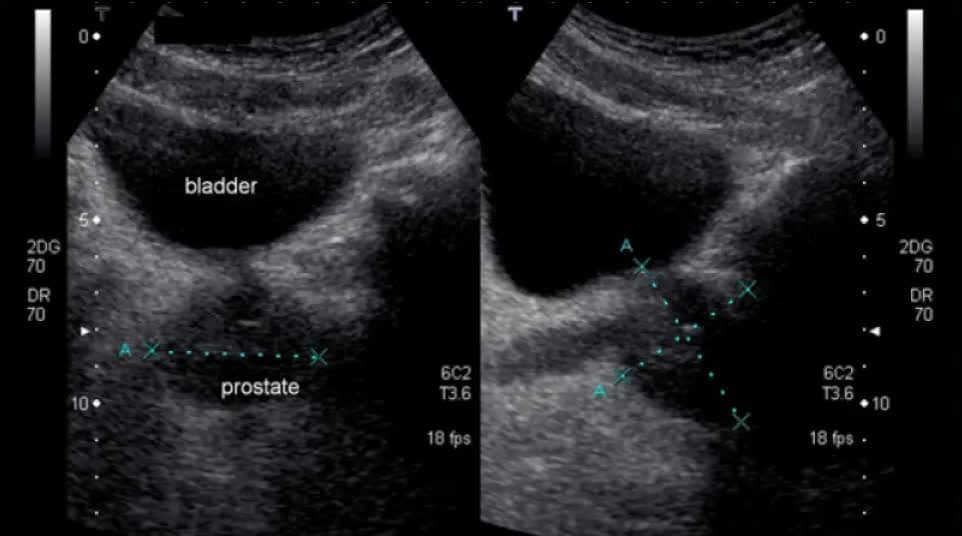

اولا ، التهاب البروستات لدي ليس مزمنًا. اصبت بالبرد أثناء الصيد ، في البداية اعتقدت أنني مصاب بالتهاب في المسالك البولية ، لأنني كثيرًا ما أجري. ثم كان هناك ألم في الفخذ ، وعدم الراحة أثناء التبول . باختصار ، ركضت إلى الطبيب ، قاموا بفحصي وجعلوني سعيدًا ، يقولون ، أنت ، يا صديقي ، مصاب بالتهاب البروستاتا. هنا ، بالطبع ، تومضت حياتي الجنسية بالكامل أمام عيني ، لقد ظننت انه لن استطيع ممارسة الجنس بعد هذا ، لكن الطبيب قال أننا سنتعالج.